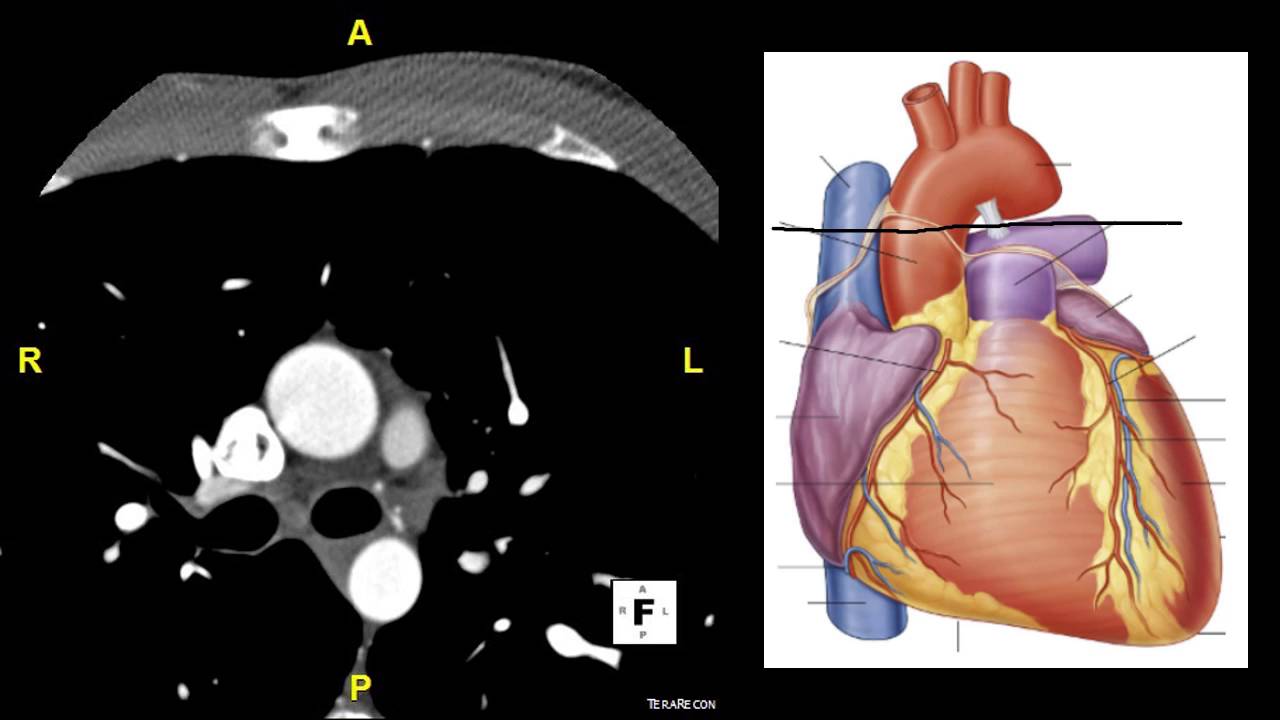

all right all right Red Nation today we're going to be talking about cardiac CT this is an area that's been really hot in CT Imaging for the last 20 years and is an area where the vendors really try and show off as far as the technology such that they can image the beating heart as you can imagine Imaging the beating heart is going to be one of the most difficult challenges from a temporal resolution perspective on the system so we're going to talk all about how cardiac CT Works different options you have for scan modes

for doing cardiac CT and also about temporal resolution on the system which is very important in the context of cardiac CT coming up here at how Radiology works so as your heart is beating the idea is that we can do CT images in order to look at the coronaries look at the whole heart look at the valves all these different applications within cardiac CT and the idea for behind cardiac CT is we want to find when the heart doesn't move as much and then we want to image quickly if you're interested you can look up